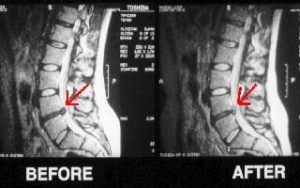

Hérnia Discal

A hérnia discal é uma patologia fisiológica e neurológica da coluna vertebral que afeta milhões de pessoas em todo o mundo. Os pacientes quando são afetados por esta patologia têm dores desesperantes e severas que desgastam todo o sistema nervoso ao longo do dia e limitações de movimentos a nível superior e inferior dependendo sempre da região afetada e são sempre na maioria da população ativa motivo para baixas médicas prolongadas. A hérnia discal tem por norma uma evolução natural derivada de posições sedentárias erráticas, excesso de esforço e quando as tensões axiais são descompensadas devido a alterações na biodinâmica da coluna vertebral tais como escolioses, hiperlordoses e hipercifoses. Resumindo, quando existe um desequilíbrio geral da estrutura (coluna), os discos intervertebrais sofrem uma maior tensão que origina a hérniação discal e pressiona a raiz nervosa. A Osteopatia é um tratamento de excelência e primário na intervenção em hérnias discais não traumatológicas. O tratamento osteopático é manipulativo e descongestionante, o que  permite retirar a pressão dobre o disco intervertebral devido ao prolapso deste sobre a raiz nervosa e consequentemente eliminar a inflamação e a dor e facilitar a irrigação sanguínea e linfática e a regeneração do nervo afetado, após esta fase, permite que o paciente volte de novo para a sua vida ativa sem limitações, diminuindo assim o número de baixas médicas por parte do paciente e intervenções demasiado invasivas.